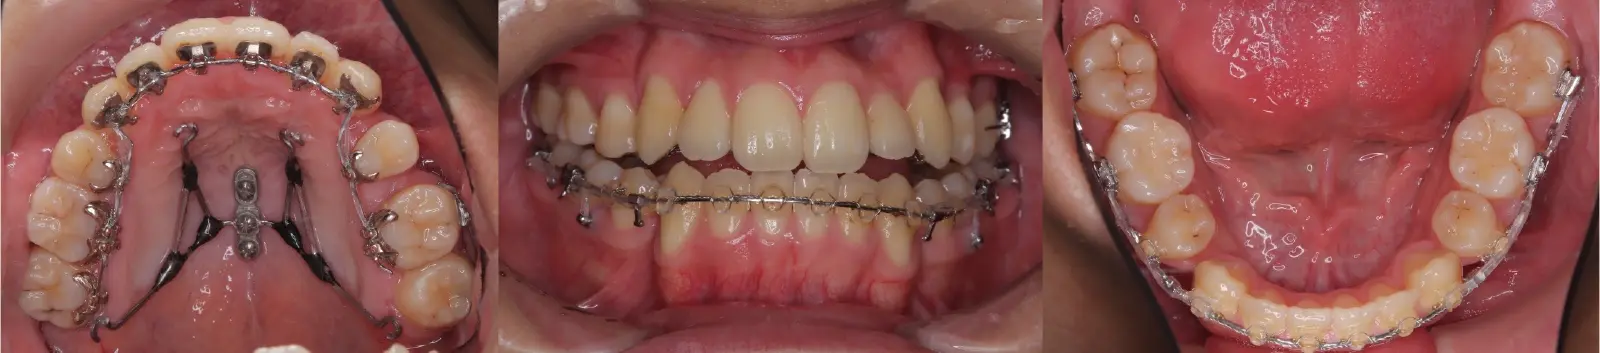

- 治療に用いた主な装置

ハーフリンガル装置(Incognito&Alexander装置)、口蓋型歯科矯正用アンカースクリュー(i-station)